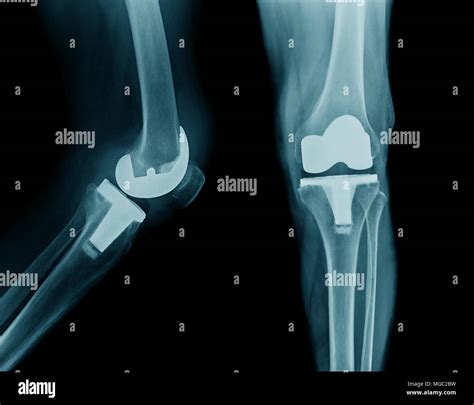

Here is an example of knee replacement images that illustrate the surgical procedure:

Knee Replacement Procedure

📸 Note: The images above are for illustrative purposes only. Always consult with a healthcare provider for personalized information.